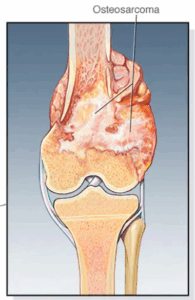

Osteosarcoma

Osteosarcoma is a kind of cancer that begins in the cells that form bones. Osteosarcoma tends to happen most often in teenagers and young adults. But it also can happen in younger children and older adults.